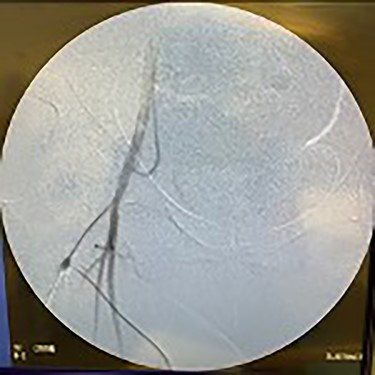

Lastly, the right iliac artery (Fig. 5) was treated using the same method (Fig. 10). After completion of the angioplasty procedure, catheter arteriogram was repeated to visualize the effectiveness of the procedure in relieving the extensive stenosis. The imaging revealed almost complete restoration of the diameter of both left and right iliac arteries (Figs 11 and 12). The distal aorta also showed improved diameter after the procedure (Fig. 9). Angiogram of both lower extremities was also performed. The catheter was passed distal to the stenosis that was previously present in the left iliac artery, to help visualize perfusion of its distal branches (Figs 13 and 14). The catheter was removed from the right femoral artery and reinserted in a distal fashion, to help visualize downstream perfusion. The right popliteal artery was well visualized on angiogram (Fig. 15), signifying strong perfusion. The patient was strongly advised to discontinue smoking cigarettes. In addition, the patient was advised to maintain regular physical exercise as tolerated and take baby aspirin daily to prevent thrombotic events.

Fluoroscopy showing dilation of the right iliac vessel post-angioplasty.